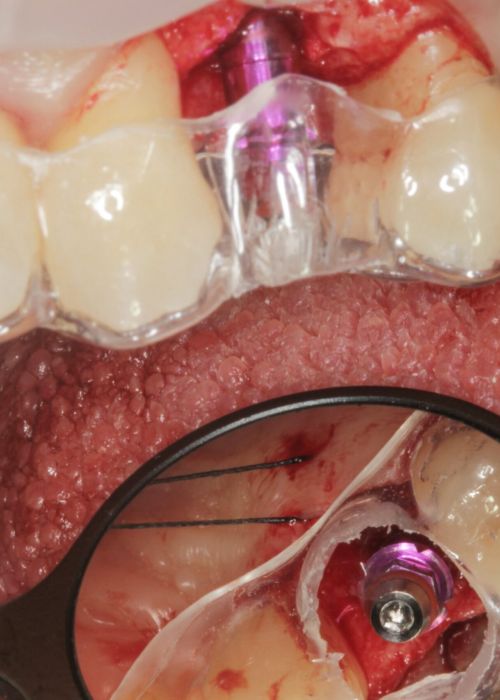

Explantación de implante mal posicionado en sector estético y regeneración posterior con injerto en bloque

Implant explantation poorly positioned in an aesthetic sector and subsequent regeneration with block grafting. Clinical case